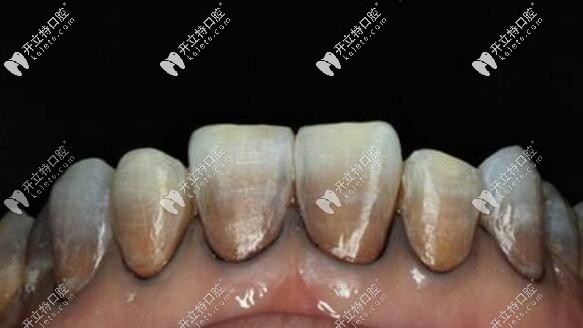

重度四環(huán)素牙照片↓↓↓

瑞典全瓷冠對圖片中的重度四環(huán)素牙有不錯效果